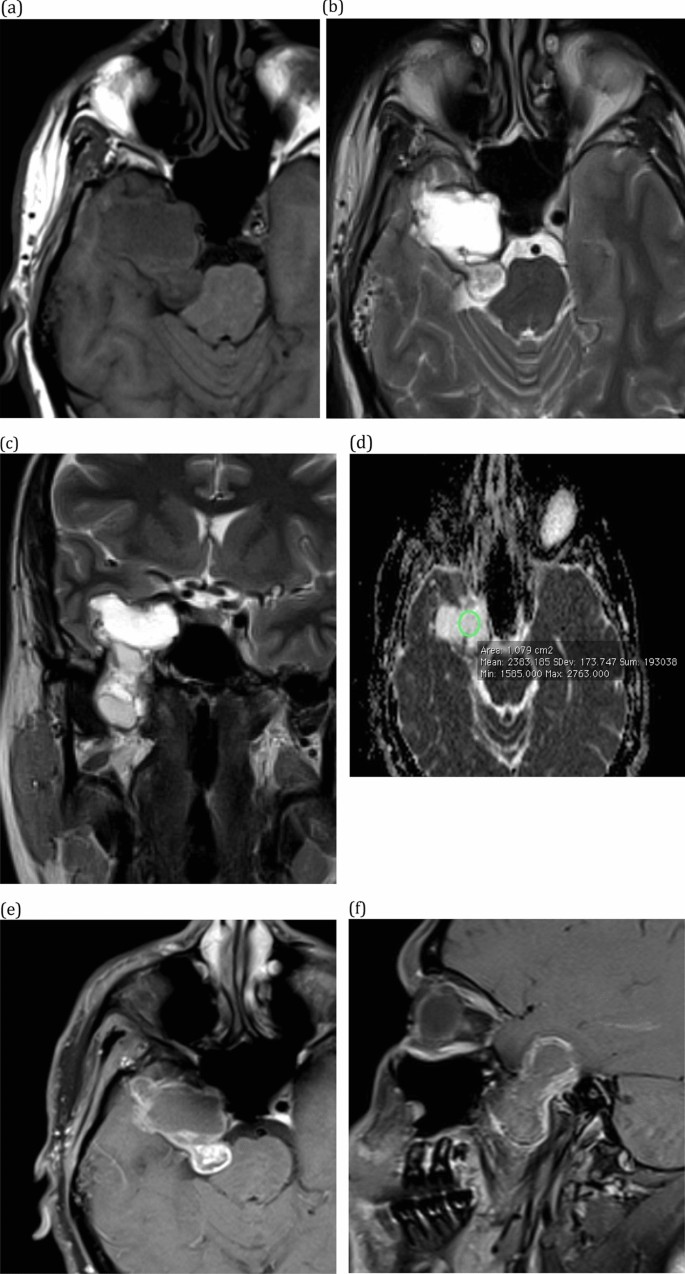

Trigeminal Nucleus Mri

Trigeminal Nucleus Mri CT Guided Gasserion Ganglion Block - Precise Saviour